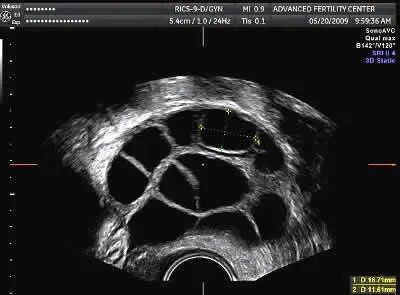

(超声波显示:从卵泡中取出一个卵子)

连接到针头的抽吸泵用于吸取卵细胞和卵泡液,抽吸将卵泡液通过管子拉出并进入试管,整个过程大约需要15分钟。